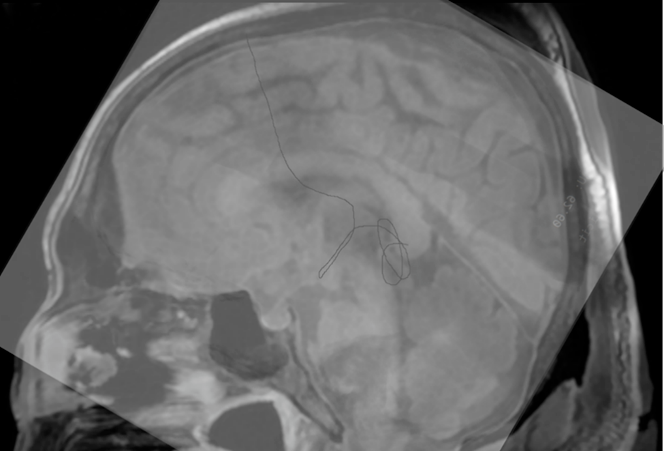

本次开展的人体实验则主要验证了通过一个颅骨创口使用MicroNeuro机器人辅助柔性内窥镜进行第三脑室造瘘与活检采样的可行性。MicroNeuro由陈达明医生操作,在抵达“患者”第三脑室深处后进行活检并在退出内镜时释放镍钛丝作为柔性内镜运动路径的参考物,待手术完成后由CT验证位置。手术前MRI图像与手术后X光对比结果表明,机器人的柔性内镜末端成功抵达第三脑室松果体区,充分验证了使用MicroNeuro在第三脑室与侧脑室手术的可行性,展示了该机器人良好的运动控制精度。

MicroNeuro成功经弯曲的脑室腔道抵达第三脑室底部,并进行活检取样。在退出过程中,MicroNeuro同时释放0.2mm镍钛丝,以标记柔性内镜行进轨迹,证明手术成功